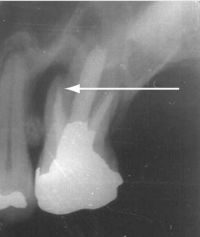

Periapical intraoral x-ray of left upper molar: a radiolucent area (arrow), denoting periapical abscess formation, is seen adjacent to one of the roots of the first upper molar, which is heavily restored and has a root canal filling.

Case 1: Progressive facial swelling

Ideal management: Progressive facial swelling secondary to oral infection requires aggressive antibiotic therapy and urgent definitive management of the underlying lesion. Patients should be started on combination amoxycillin + metronidazole or clindamycin6 and referred immediately (if possible) to the nearest tertiary hospital — preferably one with an oral and maxillofacial surgery unit.